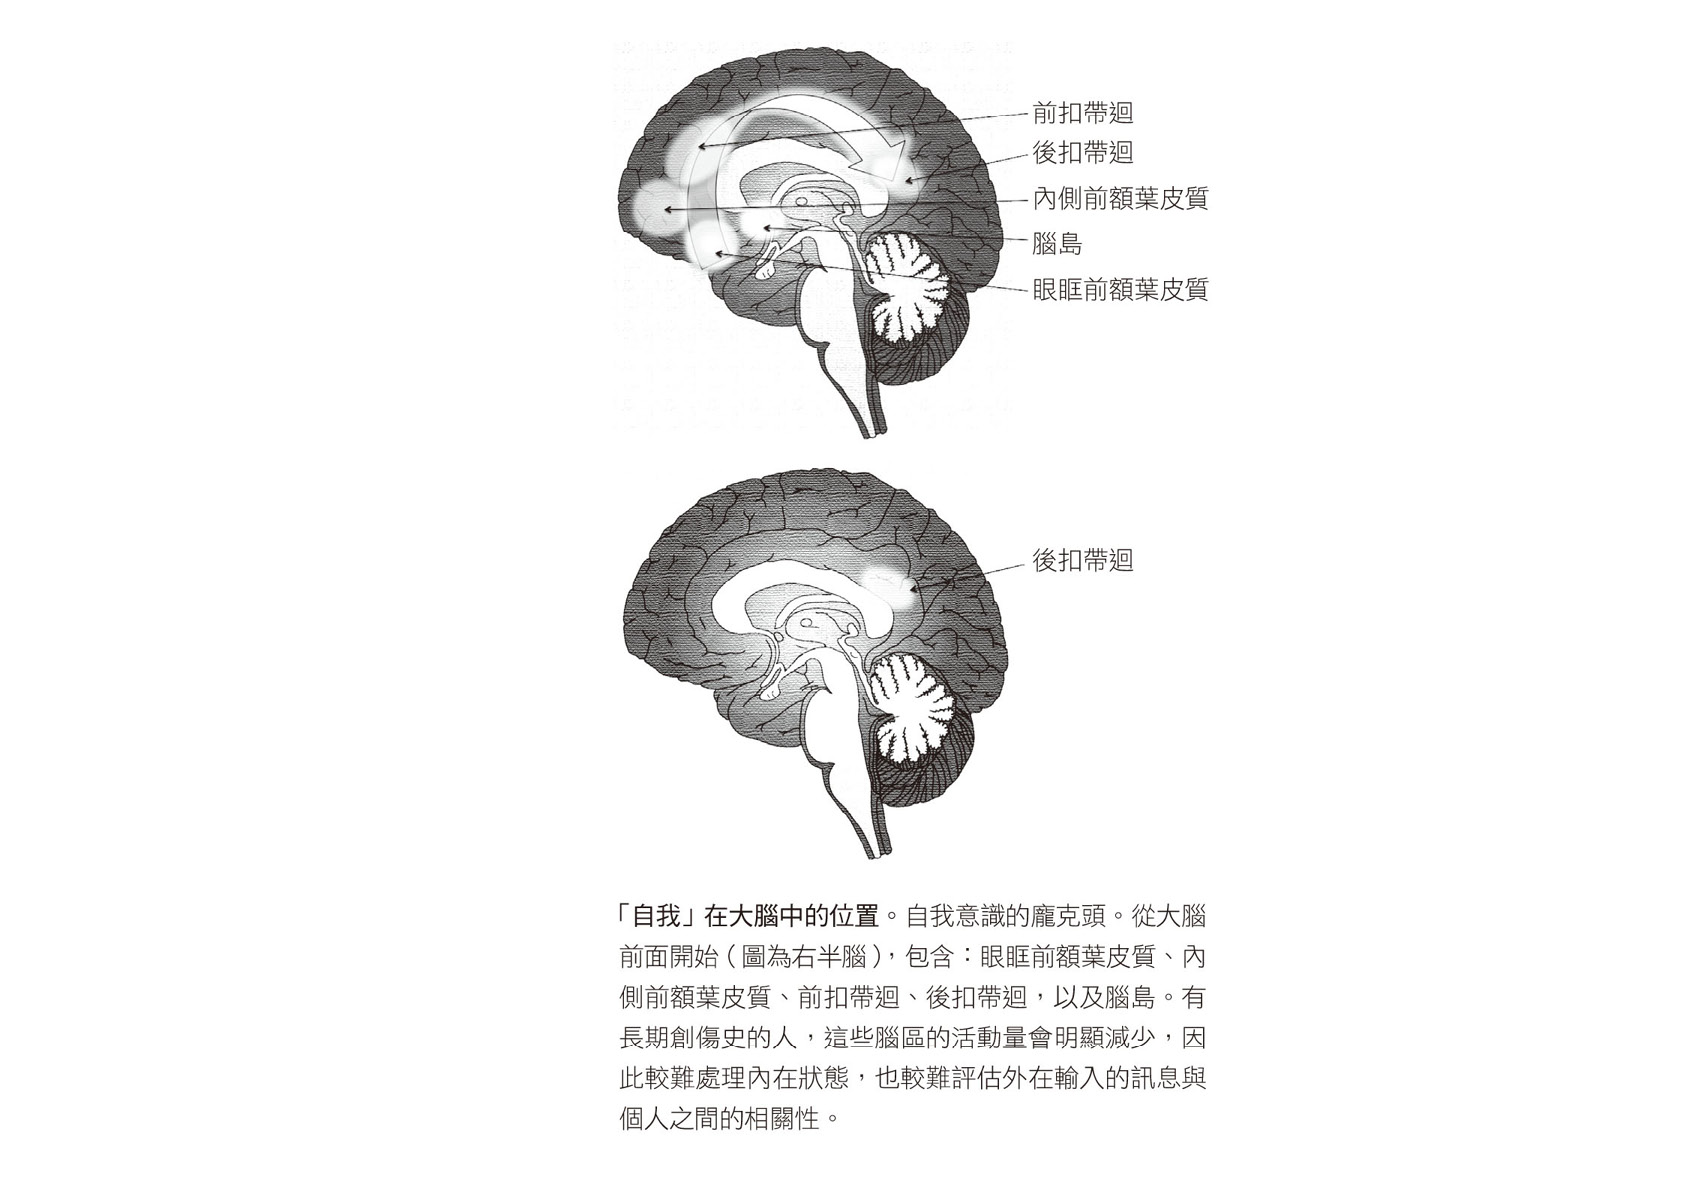

上一頁的圖說明瞭整個身體面對威脅時的反應。

拉尼厄斯從正常受試者的掃瞄結果發現,預設狀態網路活化了一些先前研究人員描述過的區域,即位於大腦中線上的結構,我喜歡稱它為「自我意識的龐克頭」。這些結構從我們眼部正上方延伸到大腦中心,再一直通到後面,所有中線結構都關係著我們的自我意識。大腦後方亮起的最大區域就是後扣帶迴,它讓我們知道自己身在何處,是我們內在的定位系統。它與內側前額葉皮質,也就是第四章我提過的瞭望臺有緊密的溝通聯繫。(這個聯繫不會顯示在掃瞄上,因為功能性磁振造影測量不到。)後扣帶迴也與幾個腦區有聯繫,這些腦區主要處理身體其餘部位輸入的感覺訊息,包括:腦島,負責將內臟送來的訊息傳到情緒中樞;頂葉,整合感覺訊息;前扣帶迴,協調情緒和思考。上述這些區域一起形成我們的意識。

至於那十八位早年遭受嚴重虐待的長期創傷後壓力症患者,他們在掃瞄上則顯出驚人的對比:腦中跟自我意識有關的區域幾乎沒有活化,內側前額葉皮質、前扣帶迴、頂葉皮質和腦島完全沒有亮起,唯一有微弱活動的是負責基本空間定向感的後扣帶迴。

這個結果只有一種可能的解釋:為了因應創傷以及後來長期持續的驚恐,患者學會關掉這些腦區,如此大腦就無法傳送伴隨著恐懼的內臟感覺與情緒。但是他們關掉的腦區,就是日常生活中負責處理所有情緒和感覺,進而形成自我意識的腦區。這真是一個悲劇性的適應行為:為了關閉可怕的感覺,他們也毀了讓自己完整活著的能力。